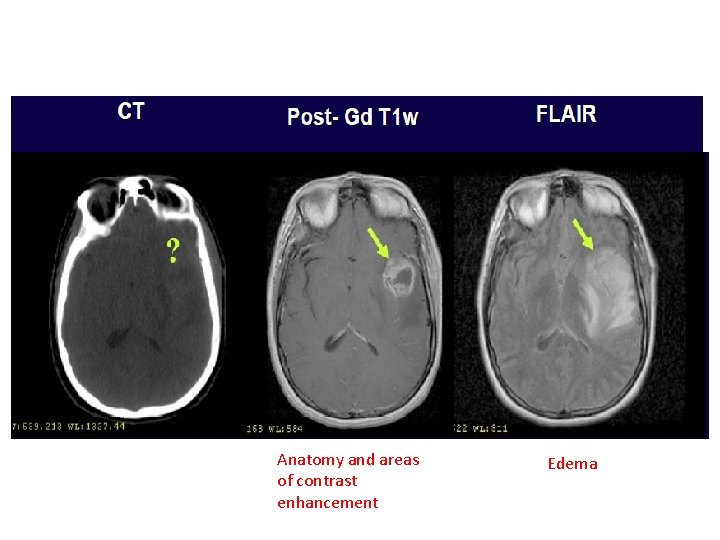

Imaging • CT-MR FusionØ Low grade tumors Ø Benign meningiomas, Ø Skull base tumors

IMAGING

Anatomy and areas of contrast enhancement Edema

• Normal post-op changes – Enhancement – Gliosis – Oedema – Tumour bed enhancement due to high protein content – Pseudoprogression • Oedema / Infiltration - difficult to interpret the response to therapy specially after steroids.